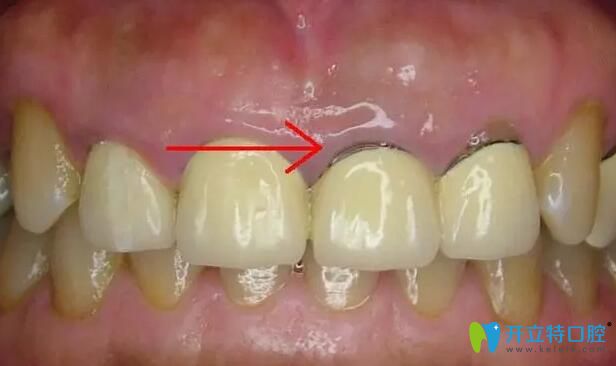

1、比較常見的牙齦黑線:這是鎳鉻烤瓷牙和鈷鉻烤瓷牙比較常出現(xiàn)的情況,這是因?yàn)閮?nèi)冠的非貴金屬材料在口腔內(nèi)氧化變成的灰色氧化物,時(shí)間長(zhǎng)了就會(huì)沉淀在牙齦上。如果不及時(shí)拆除,有可能會(huì)出現(xiàn)牙周炎、牙齦炎嚴(yán)重的也會(huì)導(dǎo)致牙齒脫落。

烤瓷牙牙齦黑線